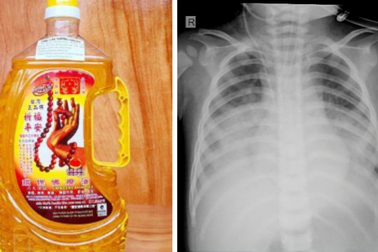

Bé 15 tháng tuổi uống nhầm dầu dùng để thắp đènBé 15 tháng tuổi uống nhầm loại dầu dùng để thắp đèn dẫn đến ngộ độc, viêm phổi nặng và phải nhập viện trong tình trạng nguy kịch.

Uống nhầm dầu thắp hương, cháu bé hơn 1 tuổi phải nhập việnBệnh viện Sản - Nhi Nghệ An cho biết, đã điều trị thành công bệnh nhi hơn 1 tuổi do uống nhầm dầu thắp hương.